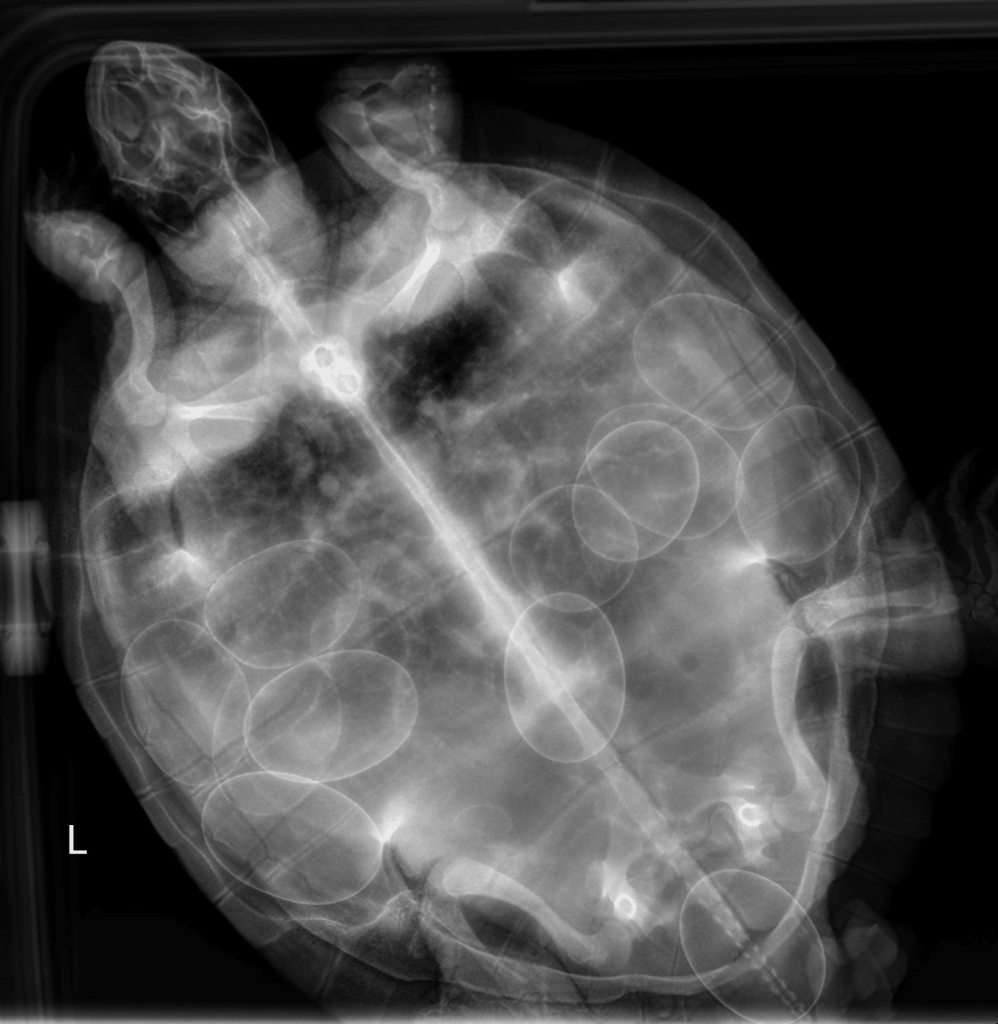

AMC’s Emergency Room veterinarians saw Shelly, a red eared slider whose owner noticed abnormal tissue protruding from her turtle’s hind end after Shelly had laid two eggs. This tissue turned out to be a prolapsed cloaca—another medical term referring to the end of the birth canal popping out while Shelly was straining to pass a stuck egg. This was a clear indication Shelly was having a great deal of difficulty passing eggs. The x-ray below shows an egg stuck half in and half out of Shelly and another twelve eggs needing to be laid!

Just like a cat or dog with dystocia, Shelly received intravenous calcium, oxytocin and pain medication. AMC veterinarians lubricated the egg to facilitate delivery, but after 24 hours, there was no progress. Veterinarians on AMC’s Avian and Exotic Pet Service then performed a more advanced procedure. Since Shelly’s eggs were unfertilized (she did not have a mate), our team removed the contents of the stuck egg using a syringe and needle. Then they broke the egg’s shell and used forceps to gently extract the remains. Shelly’s cloaca was placed back into its normal position and sutured in place. Shelly was discharged with instructions for her owner to keep track of the number of eggs laid and to monitor for recurrence of the cloacal prolapse. A few days later, the owner reported multiple eggs had been laid successfully.